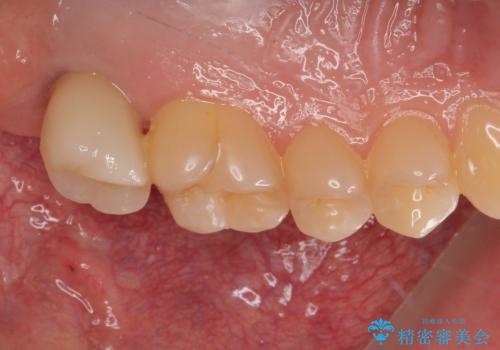

インプラントの埋入から被せものの装着まで2ヶ月で終えることができました。治療期間も短く、しっかり咬めるため大変喜んでいただきました。